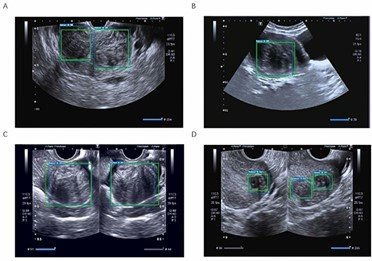

-سونوگرافی لگن: روشی که طی آن یک ابزار کوچک به نام مبدل یا داخل واژن قرار داده می شود یا از روی شکم با استفاده از امواج صوتی تصاویری از اندام های داخلی ایجاد میکند که پزشک می تواند اندازه، شکل و بافت رحم را ببیند و هرگونه رشد را ارزیابی کند.

-تصویربرداری رزونانس مغناطیسی (MRI): این نوعی از فناوری تصویربرداری پیشرفته است که تصاویر بسیار دقیقی از اندام های داخلی ارائه می دهد. این تصاویر به ارائه دهنده شما کمک می کند تا محل دقیق و ویژگی های فیبروم را تعیین کند و در صورت نیاز، درمان های کم تهاجمی را برنامه ریزی کند.